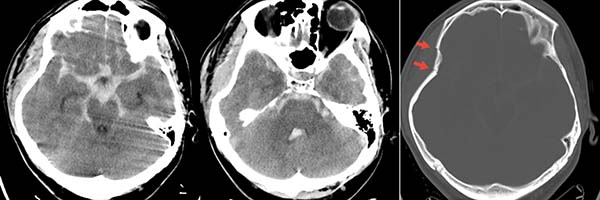

今年26岁的于先生,5月11日晚间被路人发现昏迷倒于路边,由救护车送至清华大学附属垂杨柳医院急诊科。当时无家属在场,病史不详。查体患者呈中度昏迷,GCS5分,右侧颞部头皮挫伤伴出血。双侧瞳孔直径3mm,对光反射消失。急查头颅CT显示广泛蛛网膜下腔出血,第三、四脑室积血,右侧颞骨凹陷骨折。

▲头颅CT显示

广泛蛛网膜下腔出血,脑室积血,右侧颞骨凹陷骨折